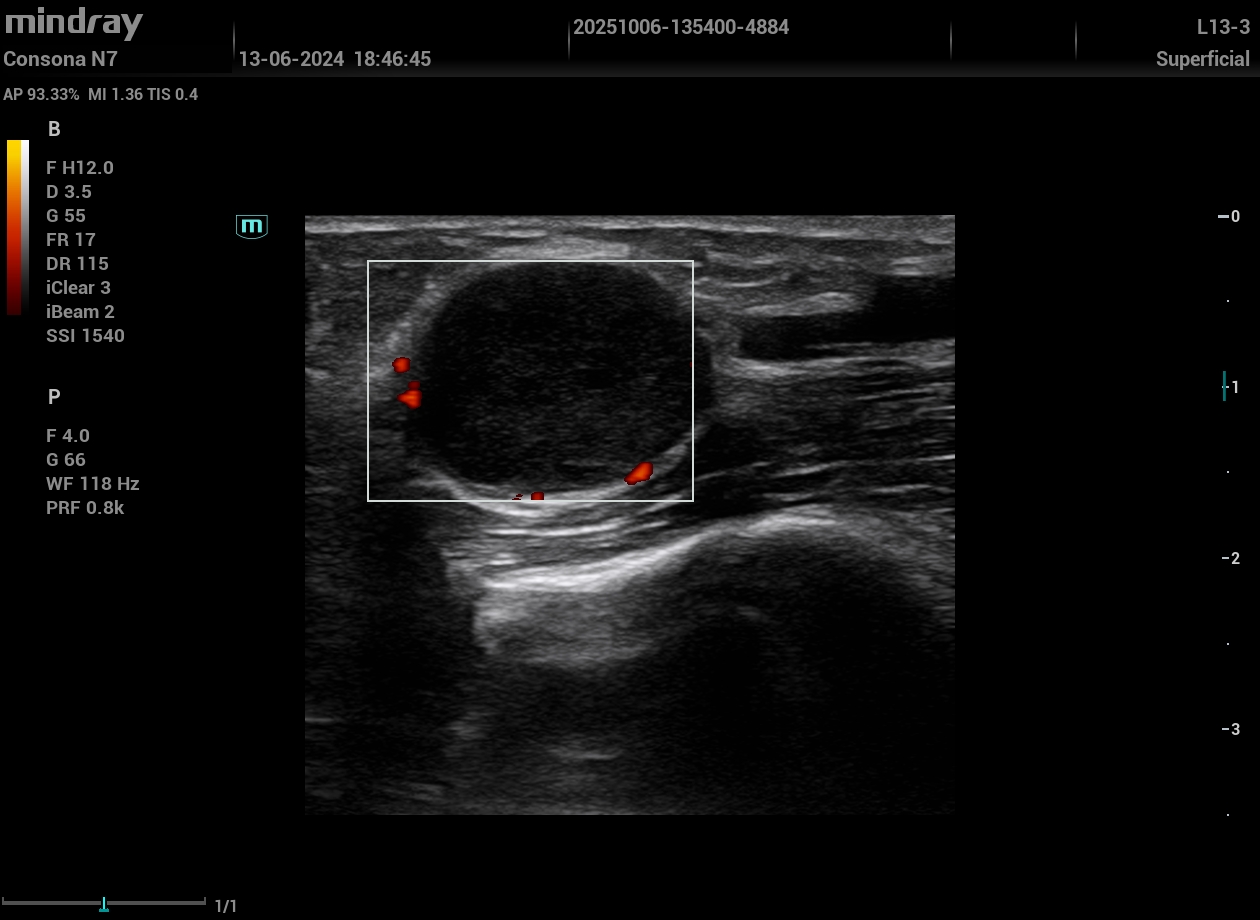

Inspirada por la rotación de una tutora en la Unidad de Riesgo Cardiovascular de un hospital, se formó al equipo en ecografía vascular e incorporó la técnica a la consulta. Se evaluó a 17 varones (50–65 años) que consultaron por disfunción eréctil sin enfermedad cardiovascular conocida y con RCV bajo-moderado por SCORE2. Se realizó una ecografía vascular aplicando el protocolo VASUS (arterias carótidas, femorales y aorta), identificando placas ateroscleróticas no detectadas antes. Estos hallazgos motivaron intensificar cambios en el estilo de vida, estrechar el seguimiento y ajustar tratamiento farmacológico.

La disfunción eréctil puede ser una señal de alarma precoz de afectación vascular. La ecografía Doppler es una técnica accesible, segura y efectiva para identificar daño aterosclerótico en pacientes con riesgo cardiovascular bajo o moderado. Su incorporación en la consulta permite una reestratificación individualizada y mejora la toma de decisiones clínicas, reforzando el papel de la Atención Primaria en la prevención cardiovascular.